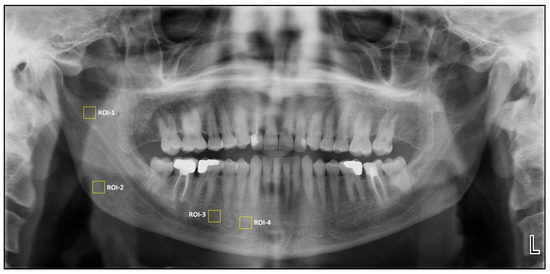

2.4. Fractal Dimension and Pixel Intensity Analysis